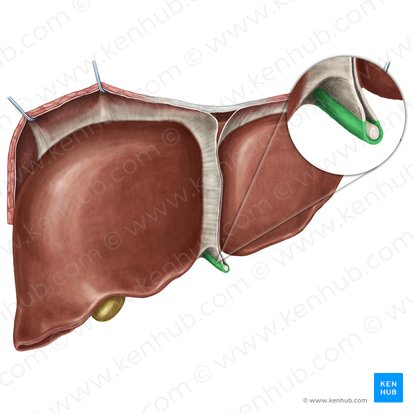

Falciform ligament

Round ligament

Fundus of gallbladder

orange highlight

Body of gallbladder

green highlight

Neck of gallbladder

yellow highlight

Cystic duct

pink highlight

Left hepatic ducts

Right hepatic ducts

Common hepatic duct

Common bile duct

Duodenal papilla within duodenum